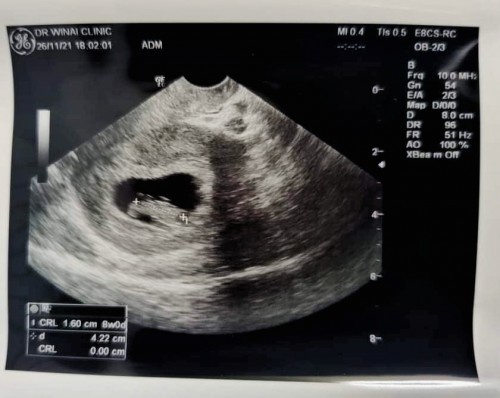

หนูน้อยของแม่ อยากเจอแว้วว🥰🥰

Post reply image